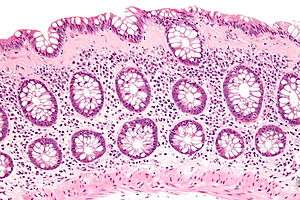

| Micrograph of collagenous colitis. H&E stain. | |

On colonoscopy, the mucosa of the colon typically looks normal, but biopsies of affected tissue usually show deposition of collagen in the lamina propria, which is the area of connective tissue between colonic glands. Radiological tests, such as a barium enema are also typically normal.[2]